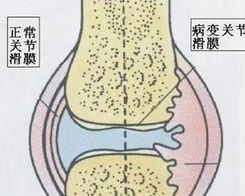

滑膜炎是指滑膜受到刺激产生炎症,造成分泌液失调形成积液的一种关节病变。常见的滑膜炎有两种:非特异性

膝关节滑膜炎是一种无菌型炎症,是由于膝关节扭伤和多种关节内损伤而引起的。滑膜的功能异常会导致关节液